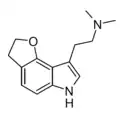

| 4,5-DHF-DMT (P-3) | artificial[16] | 4,5-(CH2CH2O) | CH3 | CH3 | 2-(3,6-dihydro-2H-furo[2,3-e]indol-8-yl)-N,N-dimethylethan-1-amine | |